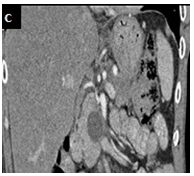

A 46-year-old male, with an alcohol-induced chronic pancreatitis, was admitted with epigastric pain. Laboratory data revealed an aspartate aminotransferase level of 98 IU/L (normal < 40), an alanine aminotransferase level of 85 U/L (normal <60) and a normal serum amylase level. Abdominal contrast enhanced computed tomography (CT) scan showed multiple pancreatic pseudocysts formations and a cystic lesion with 5,9 x 2,5 cm in diameter in the pancreatic head extending to the gastric wall which had an almost entirely intraparietal location Figure 1(A). Upper gastrointestinal endoscopy revealed bulging of the wall in the posterior portion of the gastric body, whose study by endoscopic ultrasonography confirmed the presence of a gastric intramural pseudocyst, with 55 mm in largest diameter, and with solid waste Figure 1(B). The pain resolved spontaneously, and therefore the patient was maintained on surveillance. Three months later abdominal CT showedspontaneous drainage of the intramural pseudocyst Figure 1(C).

Figure 1B Endoscopic ultrasonography: gastric intramural pseudocyst, with 55 mm in largest diameter with solid waste.